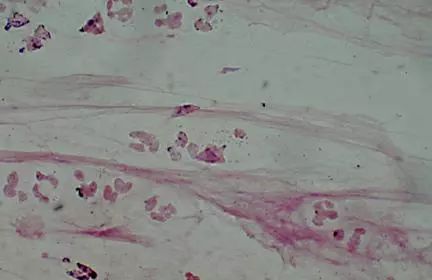

图1.13 (左)革兰氏染色显示成对和链状的革兰氏阳性球菌,(右)肺炎链球菌培养阳性。

图1.14 革兰氏染色显示肺炎链球菌。

图1.15 革兰氏染色显示流感嗜血杆菌。

图1.16 革兰氏染色显示卡他莫拉菌

开始抗生素治疗前应进行痰革兰氏染色和培养。革兰氏染色可能会观察到单一的主要微生物,尽管吸痰时厌氧菌污染可能会观察到混合菌群。